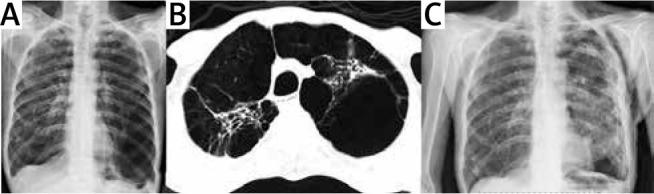

https://cdn.ncbi.nlm.nih.gov/pmc/blobs/02f3/7526494/62dc77987737/KITP-17-41808-g002.jpg

https://cdn.ncbi.nlm.nih.gov/pmc/blobs/02f3/7526494/9311fbc8e641/KITP-17-41808-g001.jpg